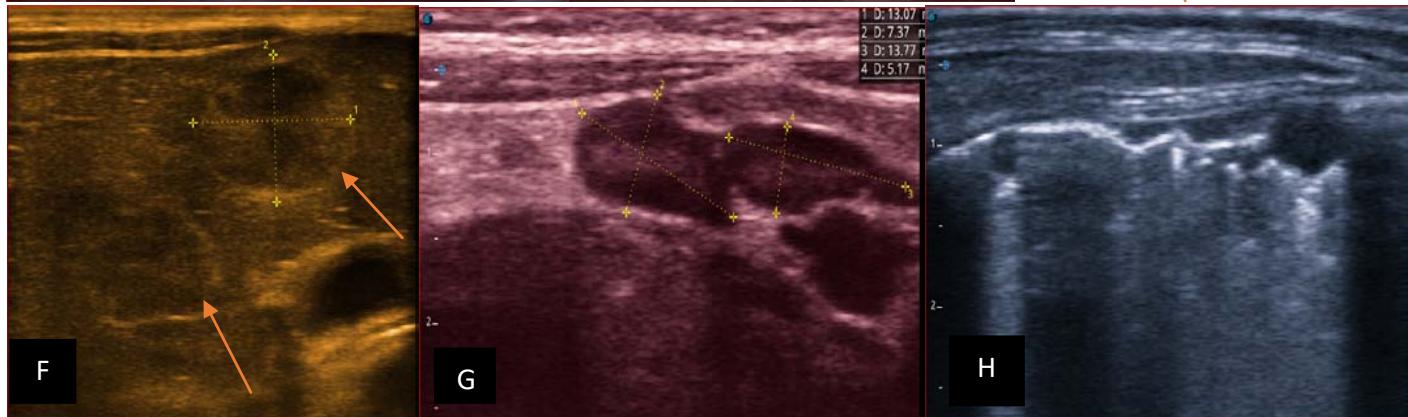

Figure 5: Abdominopelvic ultrasound control after 6 courses of chemotherapy in the same 3 year old patient with a ruptured left renal nephroblastoma; Images A, F, G, and H: show regression of the solid, endo and exo renal, left nephroblastoma mass treated with 6 courses of chemotherapy (current volume 430 ml vs) Images: B, C, and: show persistence of thrombotic permeation pan vena cava and ipsilateral renal. Image E: shows a volumetric regression of the intra-lesional hematic collection, at the tumor rupture estimated at 34.49 ml VS, Image I: represents the right kidney in B mode which is of normal echoculture. Source: Dr. Frederick Tshibasu Tshienda database.